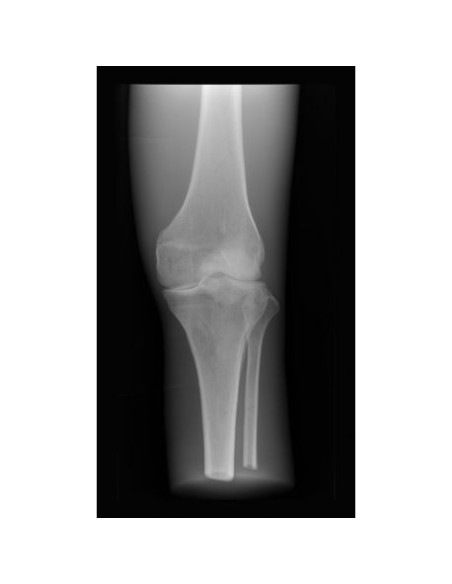

Simulatore da radiologia - Ginocchio - Opaco - Erler Zimmer 7255

Questo indispensabile simulatore medico da radiologia da l'opportunità unica di prendere immagini a raggi X di singole parti del corpo più e più volte.

Il manichino contiene vere ossa umane e permette d acquisre immagini a raggi X reali.

ll simulatore medico è perfetto per le scuole e per l'istruzione, ma anche per i tecnici medici e radiologici, dal momento che le stesse ossa possono essere sottoposte ai raggi X più e più volte in diversi contesti senza pericolo di danneggiare un paziente.

Le ossa sono incorporate in materiale plastico che è rivestito in colore opaco per nascondere le strutture interne.

Il simulatore di ginocchioi per radiologia è realizzato a mano ed è unico nel suo genere.